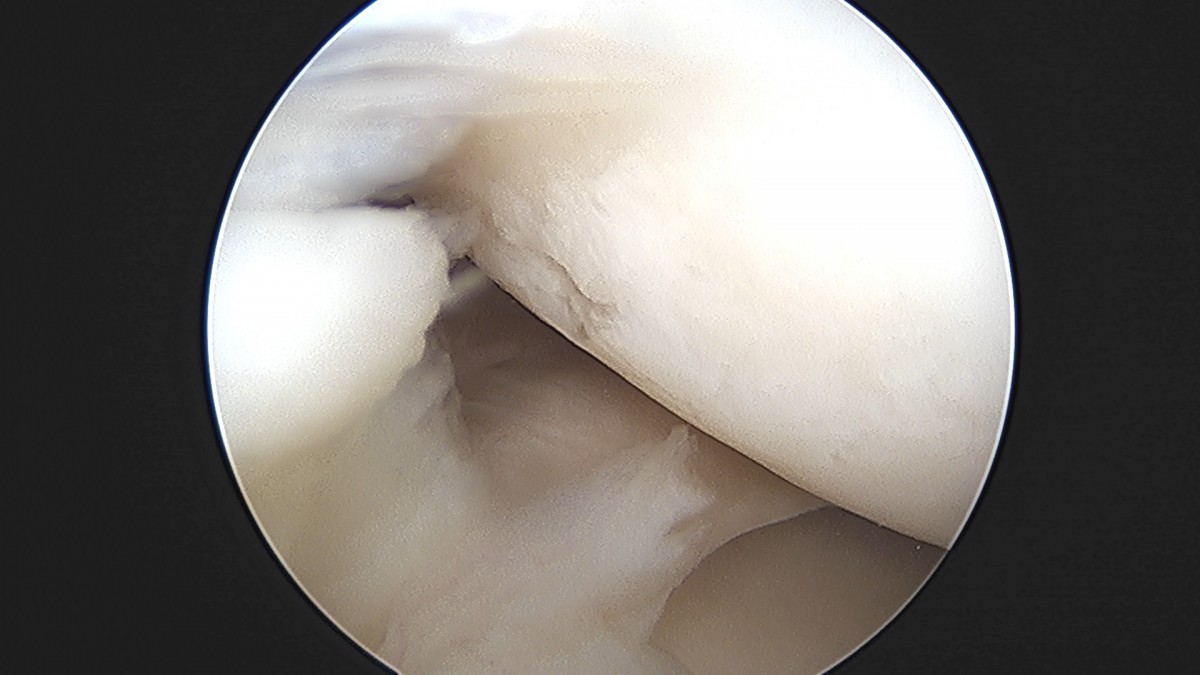

이재상원장님 무릎 낭종 제거술 김은O 환자

작성자 최고관리자 댓글 0건 조회 789회 작성일 25-09-16 15:20